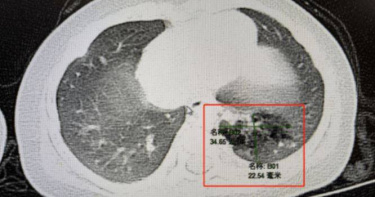

大陸24歲男子小林(化名)近日因深夜聚餐飲酒後出現劇烈嘔吐並伴隨咯血,被緊急送往奉化區人民醫院救治。經初步止血與抗感染治療後,症狀一度緩解,但停藥不久咯血再次發作。由於病因始終不明,醫師最終建議進行支氣管鏡檢查,以釐清出血根源。《寧波晚報》報導,急診檢查顯示,小林左肺存在局部支氣管擴張並伴隨感染,氣道內疑似有阻塞物,且供血血管形態異常,稍有刺激便可能引發大出血。考量患者年僅24歲,卻出現與年齡不相符的肺部病變,醫師高度警覺,認為必須進一步探查。不過,小林一度因恐懼檢查而拒絕手術,選擇保守治療。然而,止血藥物一停用,咳血症狀隨即復發,讓小林意識到問題嚴重性,終於同意接受支氣管鏡手術。手術當天,呼吸與危重症醫學科團隊在麻醉科配合下進行檢查,鏡頭深入左下肺反覆出血區域時,竟發現一枚白色塑膠筆帽卡在支氣管深處,周圍已被肉芽組織包覆,顯示異物滯留多年。更驚險的是,筆帽位置緊鄰肺動脈分支,稍有不慎恐引發致命大出血。醫療團隊事先擬定完整應變方案,細緻剝離組織後,成功將筆帽完整取出。麻醉甦醒後,小林才恍然想起,這正是自己小學六年級時不慎吸入、以為早已遺失的筆帽。醫師解釋,筆帽長期刺激氣道與周邊血管,身體逐漸「適應」,此次因劇烈嘔吐導致異物移位,才引發嚴重出血。院方也提醒,若童年曾有誤吸異物史,即使多年無症狀,日後出現反覆咳嗽、咯血或肺部感染,務必及早就醫檢查。支氣管鏡已可在無痛麻醉下進行,及早診斷,才能避免小問題演變成大危機。